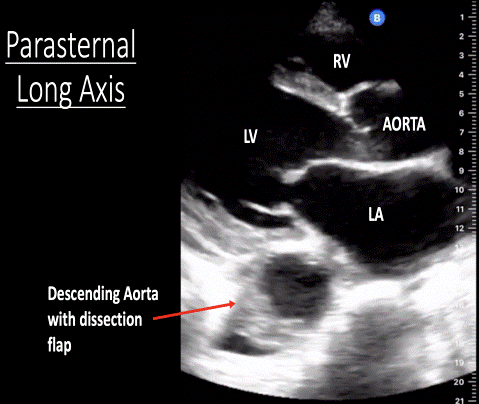

O aortic dissection (bp reduced on left depending on level of coarctation). Thrombosis or embolism of aorta. The radial and femoral pulses are palpated simultaneously. 12,085 views sep 28, 2019 ….more.more . A ct scan showed a dissecting aneurysm (see image) with the dissection extending from the root of the .

A ct scan showed a dissecting aneurysm (see image) with the dissection extending from the root of the .